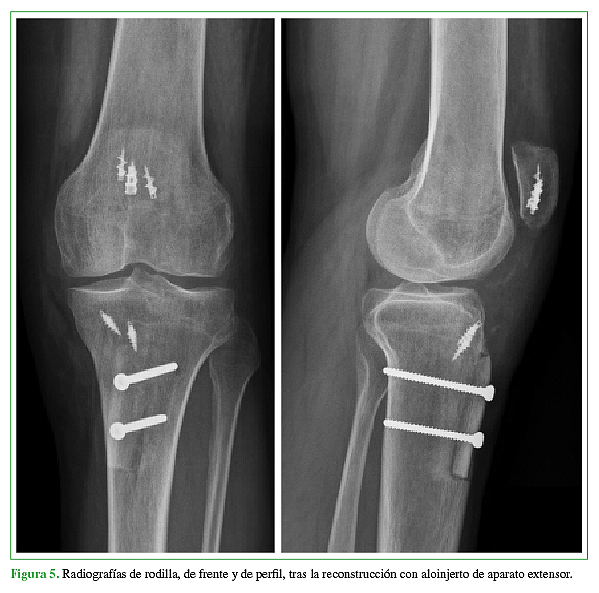

El objetivo de este trabajo es la presentación de un caso donde se realizó la reconstrucción quirúrgica del aparato extensor mediante la utilización de aloinjerto luego de haber presentado tres cirugías fallidas para la reparación del tendón rotuliano tras sufrir una lesión traumática del mismo. Se describe tanto la técnica quirúrgica como también el protocolo de rehabilitación.